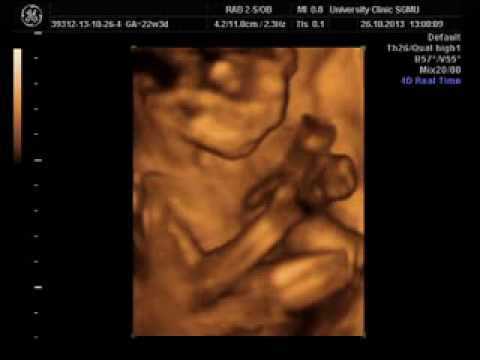

Если. УЗИ не было назначено ранее, неделя самое подходящее для этого время. Сейчас можно оценить не только состояние матки, вес, рост и состояние органов и систем, но и его предлежание, которое, как правило, является уже окончательным.

Также оценивается состояние плаценты. Если присутствует преждевременное ее старение, это чревато задержкой внутриутробного развития, поэтому крайне важно вовремя обнаружить данную патологию. Элина снимки всех животиков неделя беременности это сколько месяцев. Данный срок вашего интересного положения соответствует началу восьмого месяца беременности и середине третьего триместра. Поем и разговариваем. Вам нужно подготовиться к родам, набраться сил и энергии, успокоиться и не нервничать. Поэтому, если вы ещё не вышли в декрет, самое время оформить дородовый отпуск на работе. Больше разговаривайте с ребеночком, пойте ему свои любимые песенки, даже можно рассказывать спокойным и убаюкивающим тоном свои любимые стихотворения, просто поглаживайте живот теплыми ладонями. Пузожитель обязательно почувствует, что все эти сообщения адресованы ему. |